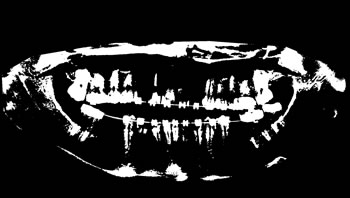

Refer to caption

Figure 3: Examples of images from the data set categories of present work: (a) Category 1; (b) Category 2; (c) Category 3; (d) Category 4; (e) Category 5; (f) Category 6; (g) Category 7; (h) Category 8; (i) Category 9; (j) Category 10.